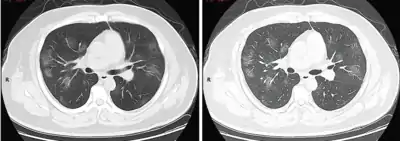

Dégâts pulmonaires

Les études en microscopie électronique et sur coupes histologiques de tissus pulmonaires (faites après autopsies) ont montré que les virions sont dans le poumon essentiellement localisés dans les pneumocytes[200].

Comme dans le cas du SARS, puis du MERS, la Covid se traduit dans l'arbre respiratoire par des lésions alvéolaires diffuses, caractérisées par des phases exsudatives et prolifératives de ces lésions, avec une congestion des vaisseaux capillaires et une nécrose systématique des pneumocytes, et très souvent une atteinte des membranes hyalines, un œdème interstitiel et intra-alvéolaire.

Les autopsies ont aussi révélé de fréquents événements thromboemboliques (« parfois cliniquement insoupçonnés au décès »)[201]. Outre une hyperplasie pneumocytaire de type 2, on a souvent observé une métaplasie squameuse avec atypie et micro-thrombus plaquettaire-fibrine[200],[202],[203],[204],[205].

L'infiltrat inflammatoire est toujours majoritairement composé de macrophages, souvent présents dans la lumière alvéolaire, souvent accompagnés de lymphocytes dans l'interstitium[200]. Des membranes hyalines se forment fréquemment, et une hyperplasie atypique des pneumocytes est également fréquemment constatée post-mortem. Le thrombus plaquettaire-fibrine des petits vaisseaux artériels peut être relié à une coagulopathie apparemment fréquente chez les malades de Covid-19 et qui selon Carsana & al (2020) devrait être l'une des principales cibles du traitement[200].